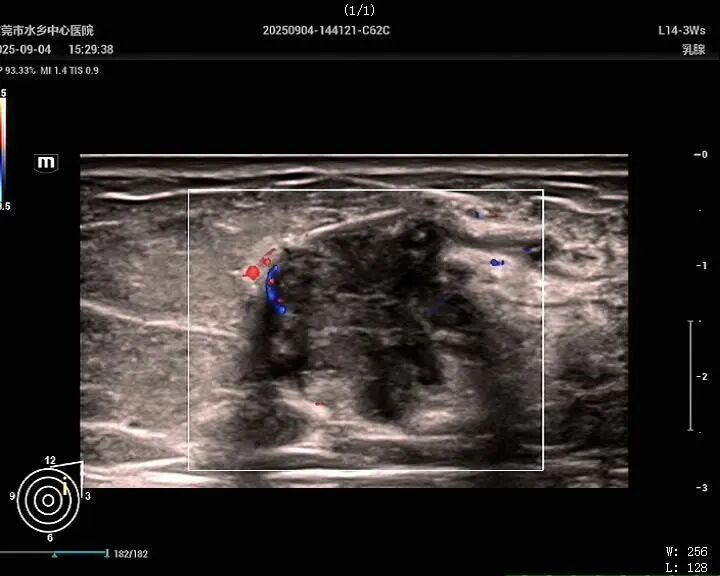

2、乳腺疾病超声精准诊疗

以分毫之辨,明善恶之分,为乳腺健康筑起精准影像防线。针对致密型乳腺、术后复查及高危人群筛查需求,开展乳腺结节分级诊断、术前精准定位及微创介入引导,显著提升早期乳腺癌检出率。同时联合乳腺科等科室开展多学科会诊,为患者制定个体化诊疗方案,真正实现早发现、早诊断、早治疗。